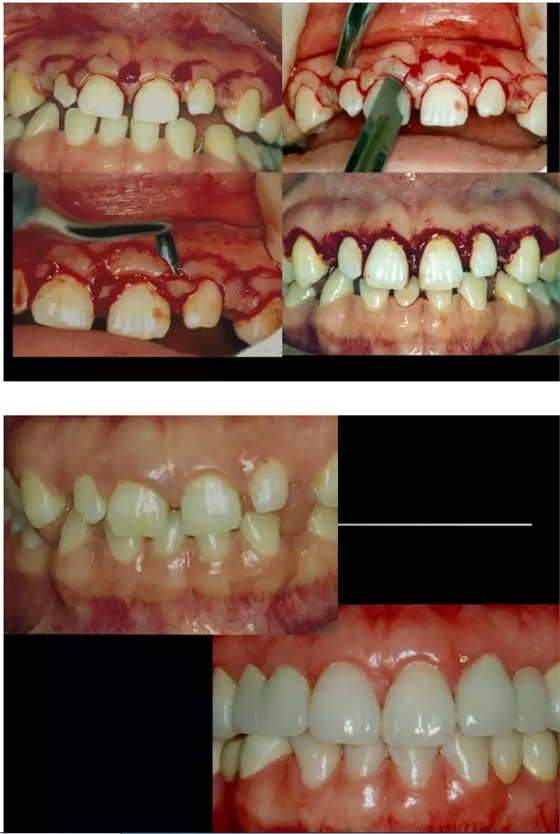

66.png

67.png

68.png

69.png